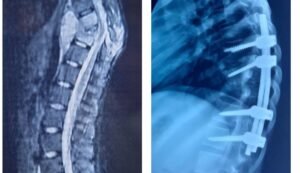

दिलीप बिल्डकॉन में माली के रूप में कार्यरत रईस खॉन की आर्थिक स्थिति कमजोर होने के कारण इशरा का इलाज आयुष्मान भारत योजना के अंतर्गत निःशुल्क किया गया। प्रारंभिक जांचों के बाद 23 जून 2025 को इशरा का ऑपरेशन किया गया, जिसमें करीब एक लीटर मवाद निकाला गया। ऑपरेशन के दौरान पेडिकल स्क्रू तकनीक और रॉड की मदद से कूबड़ को सीधा किया गया।

ऑपरेशन की सबसे बड़ी चुनौती यह थी कि हड्डी सीधी करने के दौरान रीढ़ की नस दबने से दोनों पैरों में स्थायी लकवा का खतरा था। इसे देखते हुए दिल्ली से विशेष मल्टी मोडल सिस्टम फॉर इन्ट्रा ऑपरेटिव मॉनीटर मशीन मंगाई गई, जिससे ऑपरेशन के दौरान नसों की स्थिति लगातार मॉनीटर की जाती रही। करीब दो घंटे तक चले इस जटिल ऑपरेशन में अस्थिरोग विभाग की टीम डॉ. वैभव जैन, डॉ. राहुल वर्मा, डॉ. आशीष गोहिया और डॉ. सुनीत टंडन ने नेतृत्व किया। निश्चेतना विभाग से डॉ. ट्विंकल केवल, डॉ. उर्मिला केसरी और डॉ. आर.पी. कौशल ने विशेष सहयोग दिया।